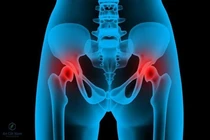

(khoahocdoisong.vn) - Để phẫu thuật thay khớp háng không chỉ căn cứ vào phim X-quang mà cần căn cứ vào triệu chứng (đặc biệt là triệu chứng đau), lứa tuổi và sau đó là điều kiện tài chính của bệnh nhân.

(khoahocdoisong.vn) - Hoại tử vô khuẩn chỏm xương đùi là tình trạng chỏm xương đùi bị phá hủy mà nguyên nhân là do thiếu nuôi dưỡng. Nguyên nhân gây bệnh có thể do chấn thương của khớp háng (gãy cổ xương đùi, trật khớp háng...), uống nhiều rượu, hút nhiều thuốc lá, lạm dụng corticoid, bệnh lý mạn tính toàn thân...

(khoahocdoisong.vn) - Người cao tuổi khi bị ngã không nên sợ phẫu thuật vì nằm thêm một ngày là bệnh thêm nặng. Việc thay khớp háng thành công sẽ giúp người cao tuổi bị té ngã có thể phục hồi sức khỏe và đi lại được.